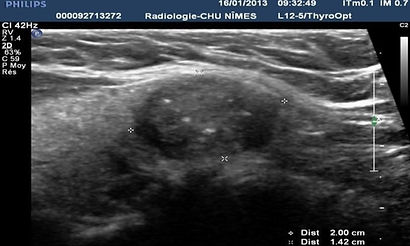

Microcalcificaciones

Fosas hiperecoicas, redondeadas o raramente lineales que miden menos de 1 mm de diámetro sin cono de sombra o artefacto en cola de cometa.

Hay que tener en cuenta su número y su agrupación (al menos 5).

No confundir las microcalcificaciones con las imágenes de tipo coloidal a nivel de los nódulos.